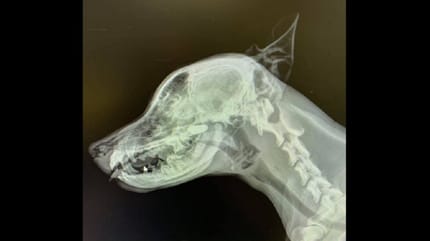

La radiografía del cráneo fue clave.

Llevaron a su perro al veterinario porque no paraba de estornudar intensamente y a la inversa. En la radiografía, se desveló el motivo.

El perro de la radiografía es un cachorro de tres meses de edad que llegó hace dos años a consulta por problemas respiratorios

Así lo evidenciaban sus estornudos constantes y a la inversa, es decir, como si estornudara "para adentro".

En una primera exploración, el veterinario no encontraba la causa. El examen oral parecía normal y en las radiografías torácicas no había nada destacable. Así que decidió hacerle una radiografía lateral del cráneo.

Según relata I Love Veterinary en su muro de Facebook, ese último escáner dio con la clave: el cachorro se había tragado una piedra y estaba alojada en la nasofaringe, de ahí esos estornudos diferentes.